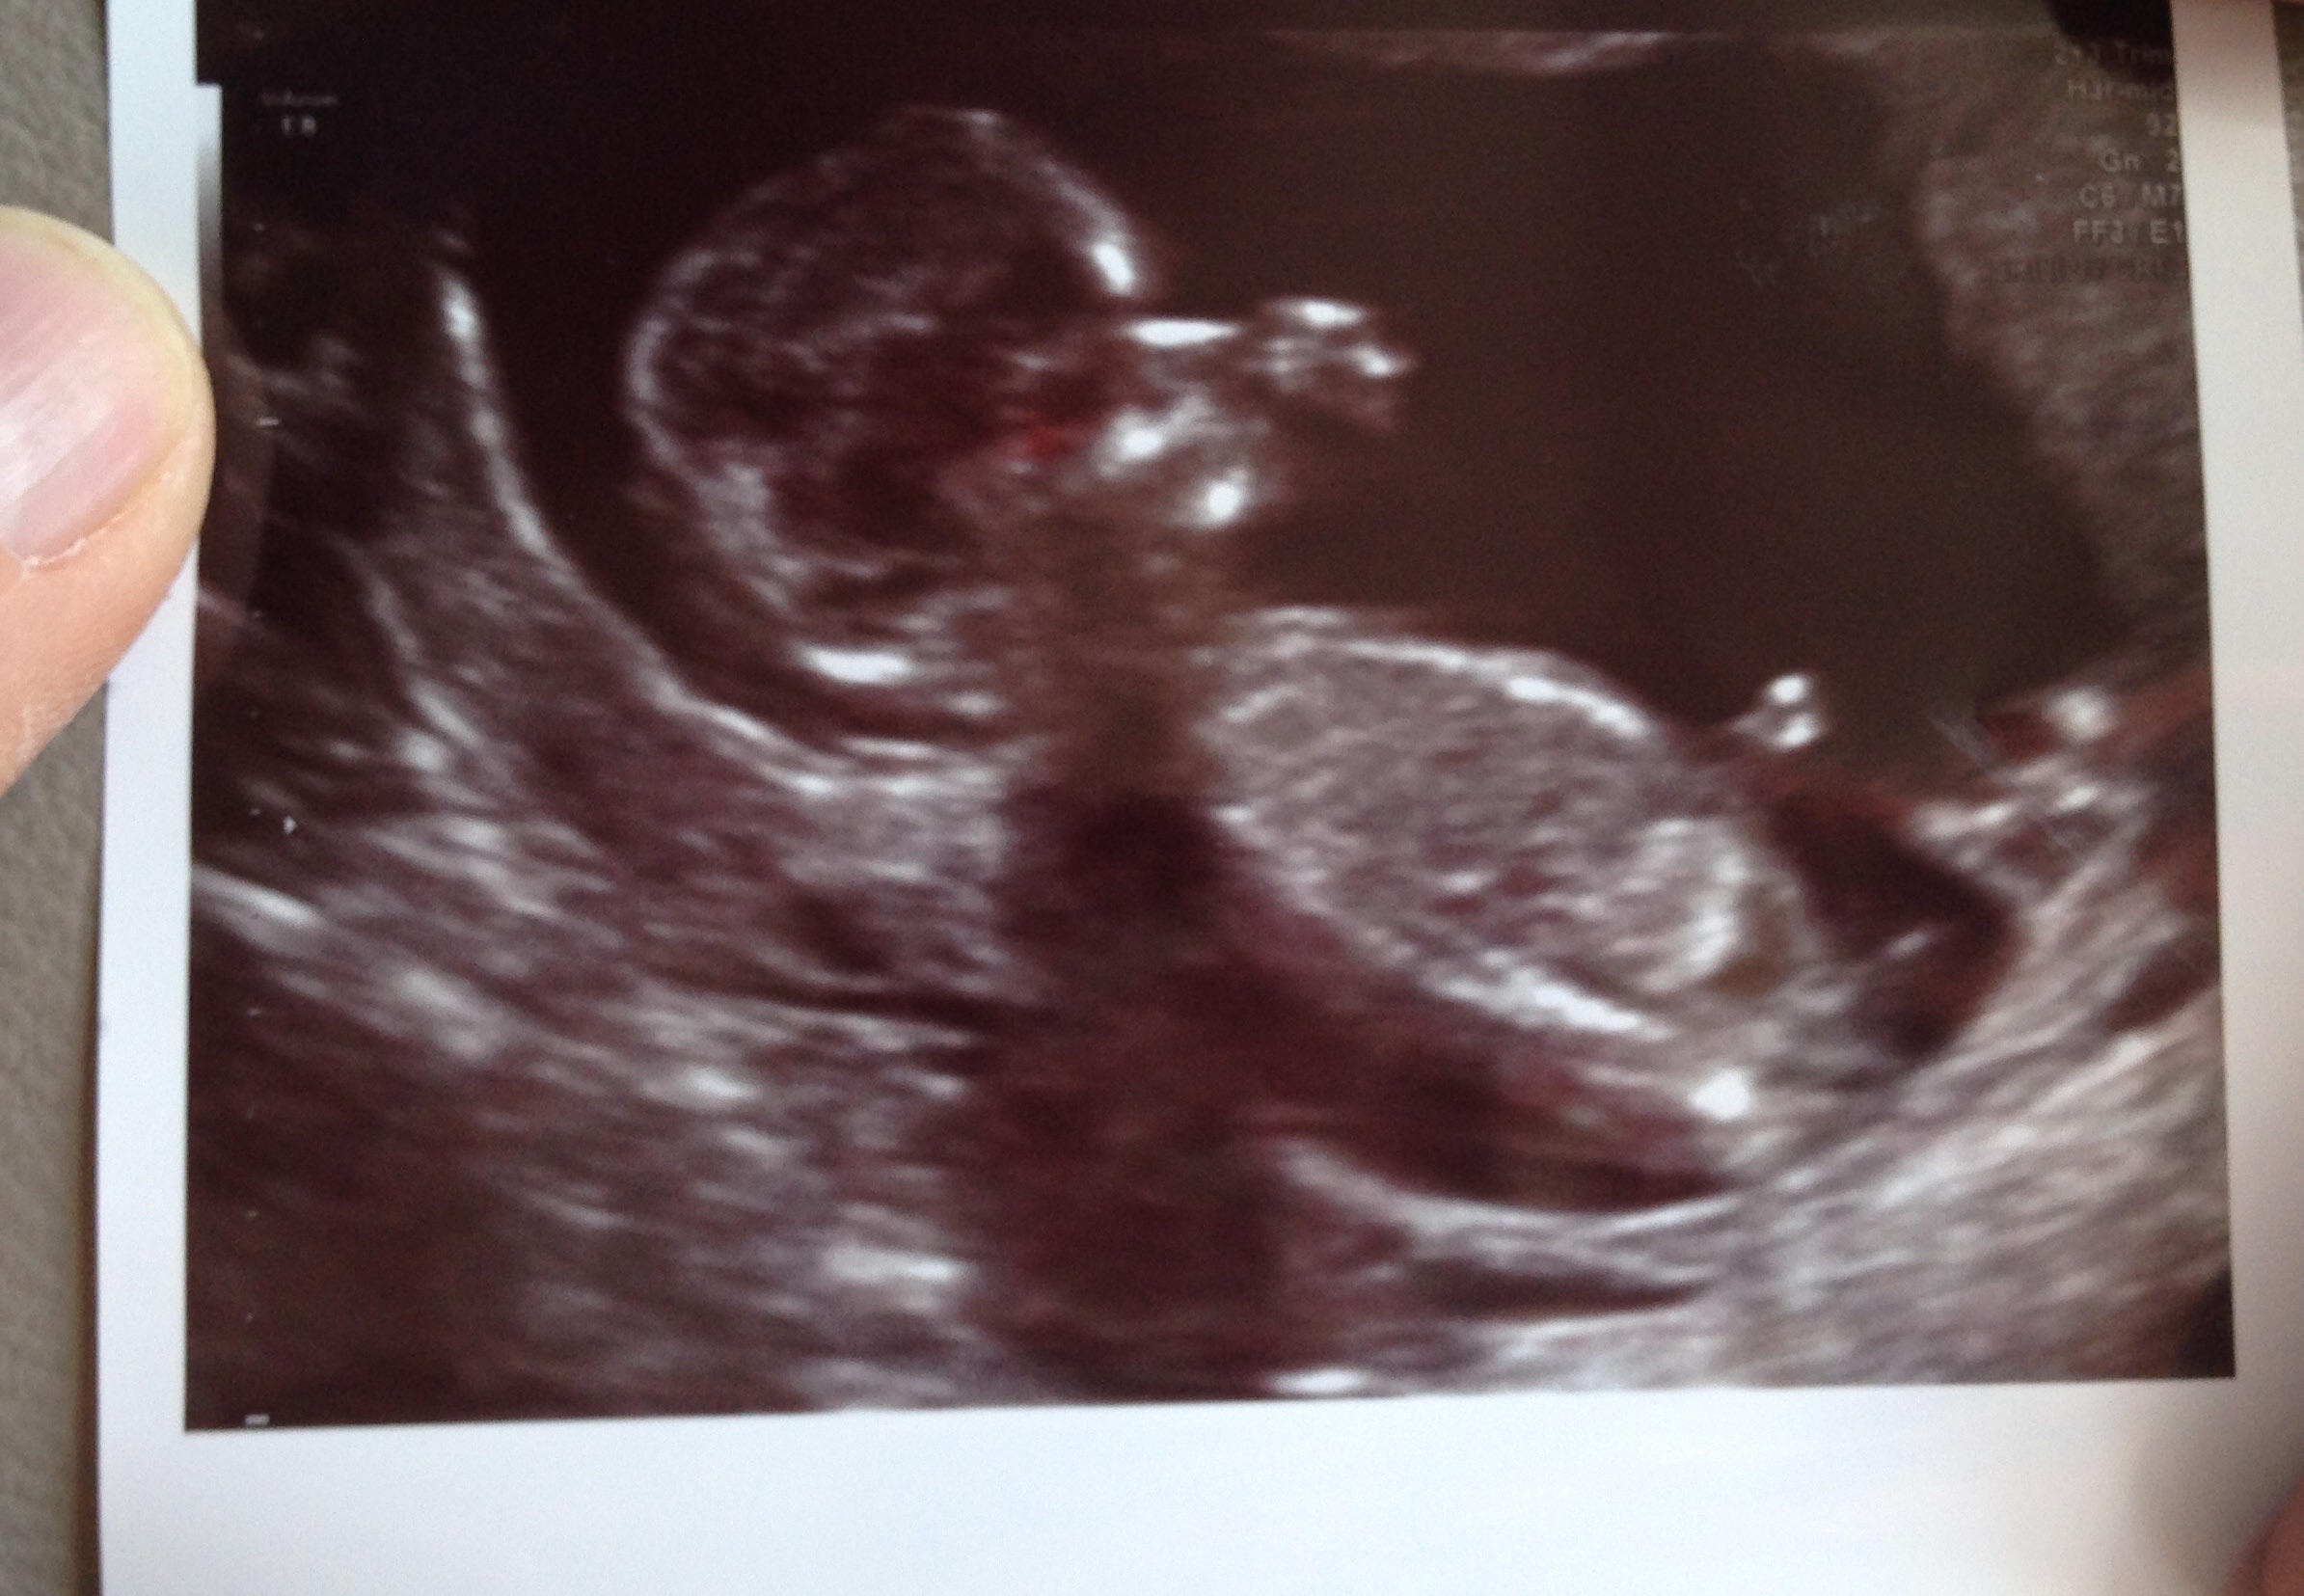

11 weeks and 2 days. This appointment was with my high risk specialist, I hope her nub theory guess was right :x so in love & super happy we got a 3d/4d.